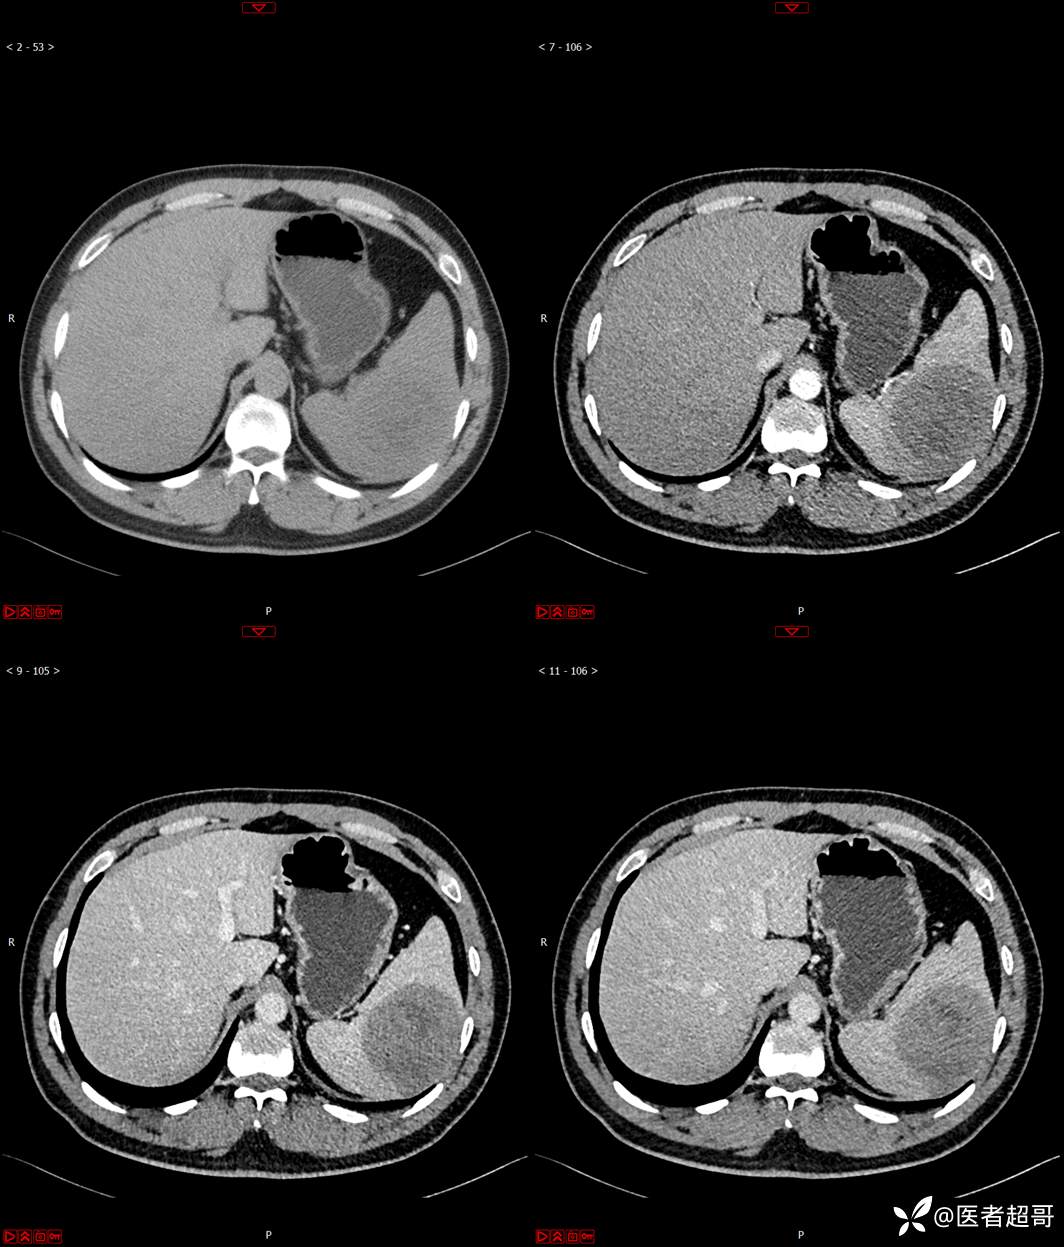

【影诊笔记596】脾脏占位01,你的病谱能网住吗?请分析,留言查询病理及术程!

主 诉:发现脾占位2月余。

现病史:患者2月余前体检彩超提示脾占位性病变,未予特殊诊治,2023.12.1于潍坊市坊子区人民医院行肝胆胰脾MR平扫提示脾脏占位性病变,左肾小囊肿,现患者无腹胀、腹泻,无恶心呕吐,无胸闷憋气等症状,今为求进一步治疗,患者来我院就诊,门诊以“脾占位性病变”收入院。患者自发病以来,一般情况可,神志清,精神可,饮食、二便正常,睡眠可,体重体力无明显改变。